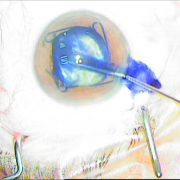

ιριδικής στήριξης

Sun Set Syndrome

πίσω από την ίριδα

ζώνης 5 ωρών

φακού